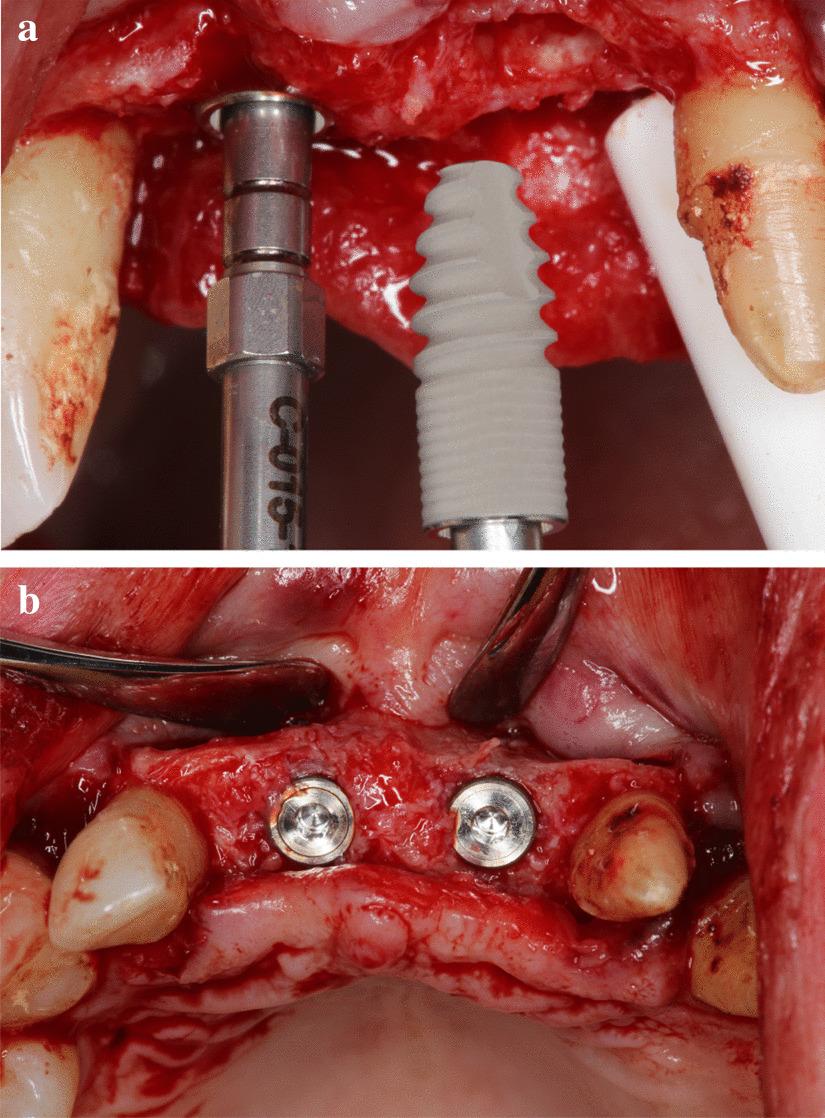

A total of 9 teeth were extracted from 5 patients. The extracted teeth were prepared immediately with the Bonmaker device. The extraction sockets were filled up with ATB powder. Six months after extraction, standardized intraoral x-rays and CBCT scans were performed. Re-entry was performed under local anaesthesia. Core biopsies were harvested for histological analysis and implants were placed.

从 5 名患者中总共拔出 9 颗牙齿。用 Bonmaker 设备立即对拔出的牙齿进行准备。用 ATB 粉末填充拔牙窝。拔牙后 6 个月,进行标准化的口腔内 X 光和 CBCT 扫描。在局部麻醉下进行再进入。采集核心活检进行组织学分析并植入种植体。